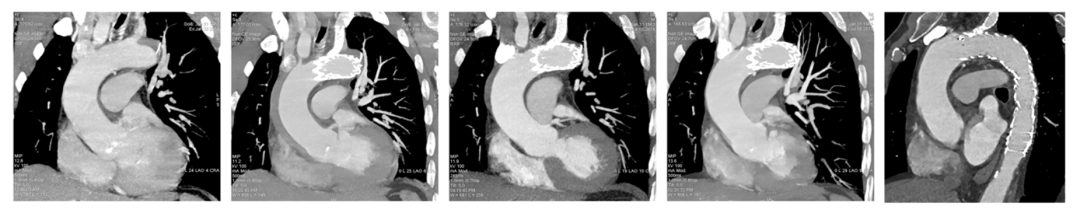

LLTEVAR多中心研究解读及围术期危险因素分析

主动脉夹层分型中,B型夹层约占全部夹层的1/3~2/3,且近端破口多位于左锁骨下动脉(LSA)附近(2区或3区)。按照现行指南,当TEVAR需要覆盖LSA时,推荐进行血运重建。重建方法包括分支支架、开窗、平行支架、转流等,各中心经验各异。激光原位开窗是其中一种可选技术,但围术期并发症及其危险因素尚缺乏大样本数据。

近期,上海交通大学医学院附属第九人民医院血管外科团队牵头国内五家中心,完成了一项前瞻性多中心单臂研究(LLTEVAR研究),评估激光原位开窗重建LSA在急性B型夹层TEVAR术中的安全性,并探索围术期严重不良事件的危险因素。本文将对研究设计、主要发现及临床启示进行解读。

LLTEVAR研究(LSA Reconstruction With Laser-Assisted Fenestration During TEVAR)是一项前瞻性、多中心、单臂临床试验,共纳入国内5家中心2020年至2022年期间收治的急性B型夹层患者。

II/III型弓(即弓顶距离无名动脉开口较远,弓部弯曲度大)会增加TEVAR操作难度,尤其在原位开窗时,激光方向控制、导丝通过、支架对位等步骤更具挑战。复杂夹层本身病情危重,需紧急干预,两者叠加显著推高风险。